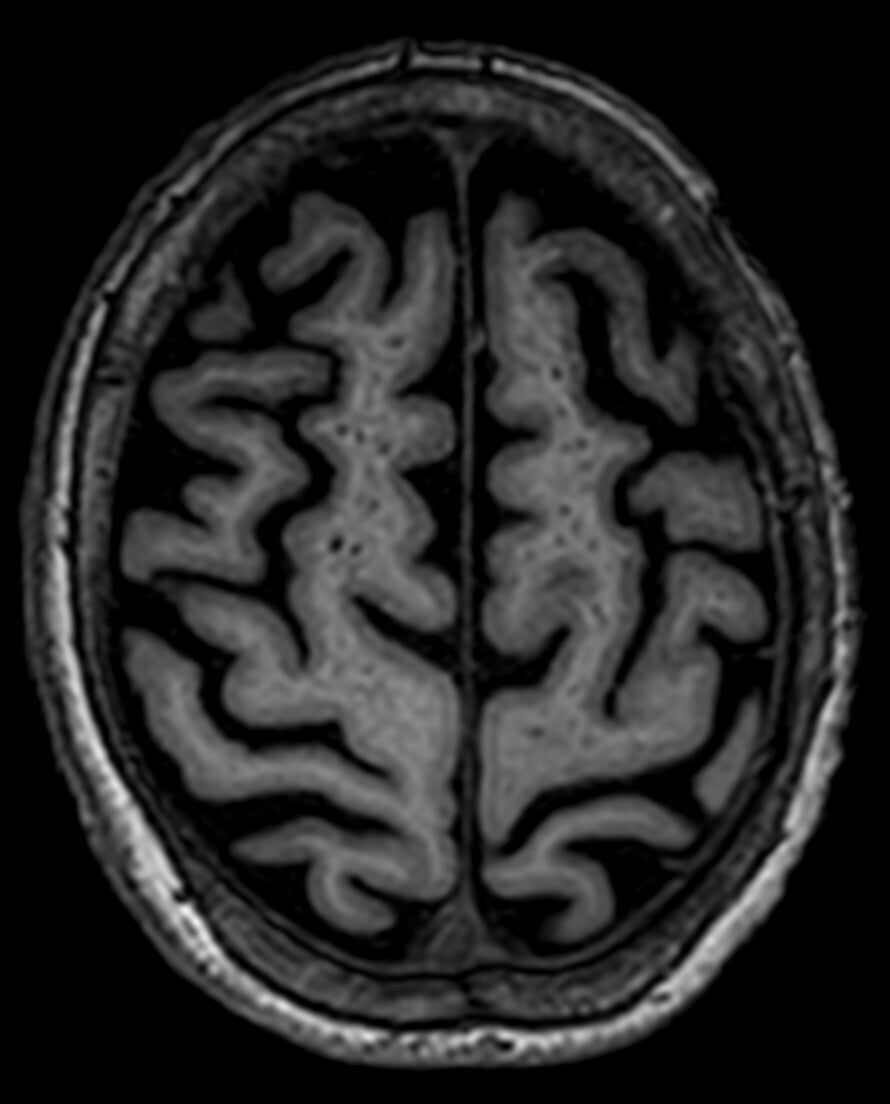

Characteristic appearances of 3 Tesla MRI imaging at a vault slice in a brain acquisition. In the first column, a picture of a microstarry sky in T1 acquisition is clearly evident and indicative of a miliary cysticercosis portrait, with multiple hollow cavities. In the second column, the corresponding snapshot in T2 is that of a myriad of point-like multiple dots, appearing as the hyperintense picture of the liquid inside the microcysts, being of the same liquor's density.

T1 (left)- and T2 (right)-weighed MRI appearance of distal cysticercal formations                     ST elevation of Prinzmetal angina